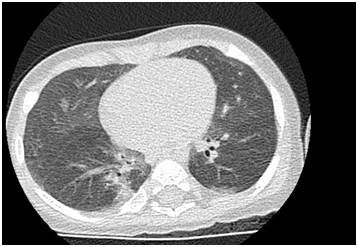

A high-resolution computed tomography (CT) scan of the lungs is often useful in the diagnosis of NEHI, showing a characteristic pattern called ground glass opacities. The lungs also show areas that are inflated to different extents, with some areas being overinflated and some underinflated, creating a mosaic pattern on CT.3

After reviewing 23 biopsy proven NEHI CTs and 6 CTs from other patients with child conditions, investigators have reported a more “classic” NEHI pattern consisting of ground-glass opacities in the right middle and lingual and air trapping in the lower lobes. The CT sensitivity and specificity to diagnose NEHI in this study was 78% and 100%, respectively.

This is report of a 1 year old girl who was born at term and had normal antenatal scans. She was diagnosed to have supraventricular tachycardia in perinatal period. SVT was labelled AV nodal re-entrant tachycardia. An echocardiogram showed a structurally and functionally normal heart. She was started on flecanide for management of SVT. She was readmitted to hospital at five months of age with bronchiolitis. This was a clinical diagnosis of bronchiolitis without any isolation of bacteria or virus. She required oxygen for next week through day and night with attempts at weaning being unsuccessful. She was therefore discharged home on oxygen at 0.5litres per minute. A repeat echocardiogram did not reveal any structural or functional abnormality. At this point, investigations for interstitial lung disease were also started. All investigations were normal apart for CT chest findings. CT chest reported patchy, predominantly central and dependent ground glass/ airspace opacification involving all lobes of both lungs. The central para mediastinal distribution of the ground glass opacification was suggestive of Neuroendocrine Hyperplasia of Infancy (Figure 1).

Figure 1 CT Chest.